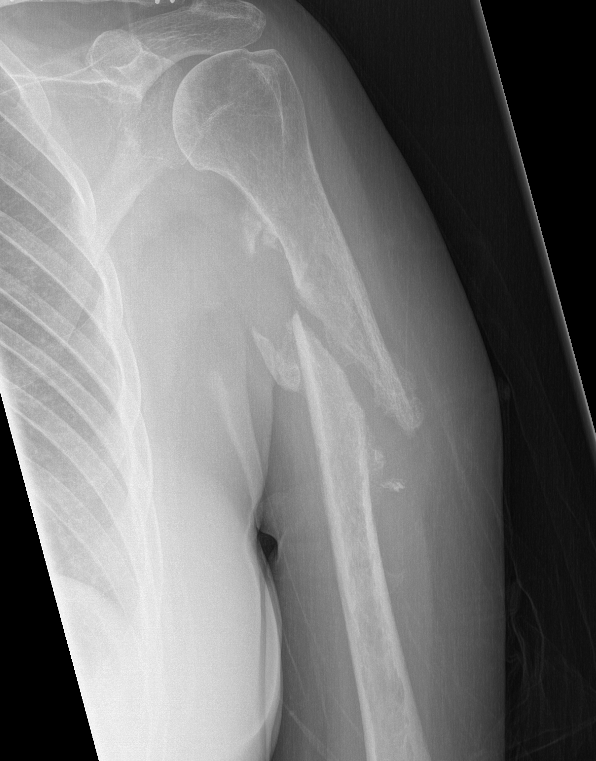

Humerus shaft nonunionHumerus nonunion

Nonunion in a proximal humerus shaft fracture treated nonoperatively

NonunionHumerus nonunion